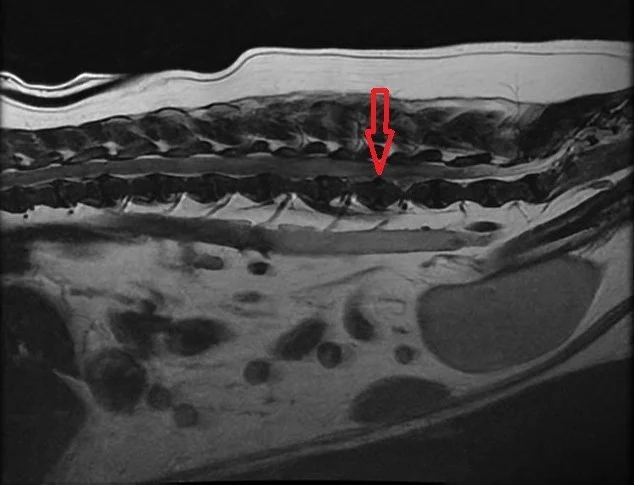

Diagnosis: Disc Herniation at L4-5, with Hemorrhage from L4-L6

This MRI image shows spinal cord compression at L4-6 with hemorrhage. The arrow is pointing to the surgical site, L4-5.

During the same day emergency consultation, Dr. Julianna Mannix ordered a thoracolumbosacral MRI. The diagnosis was immediately clear: a disc herniation at L4-5 with hemorrhage from L4-L6 was causing her clinical signs.